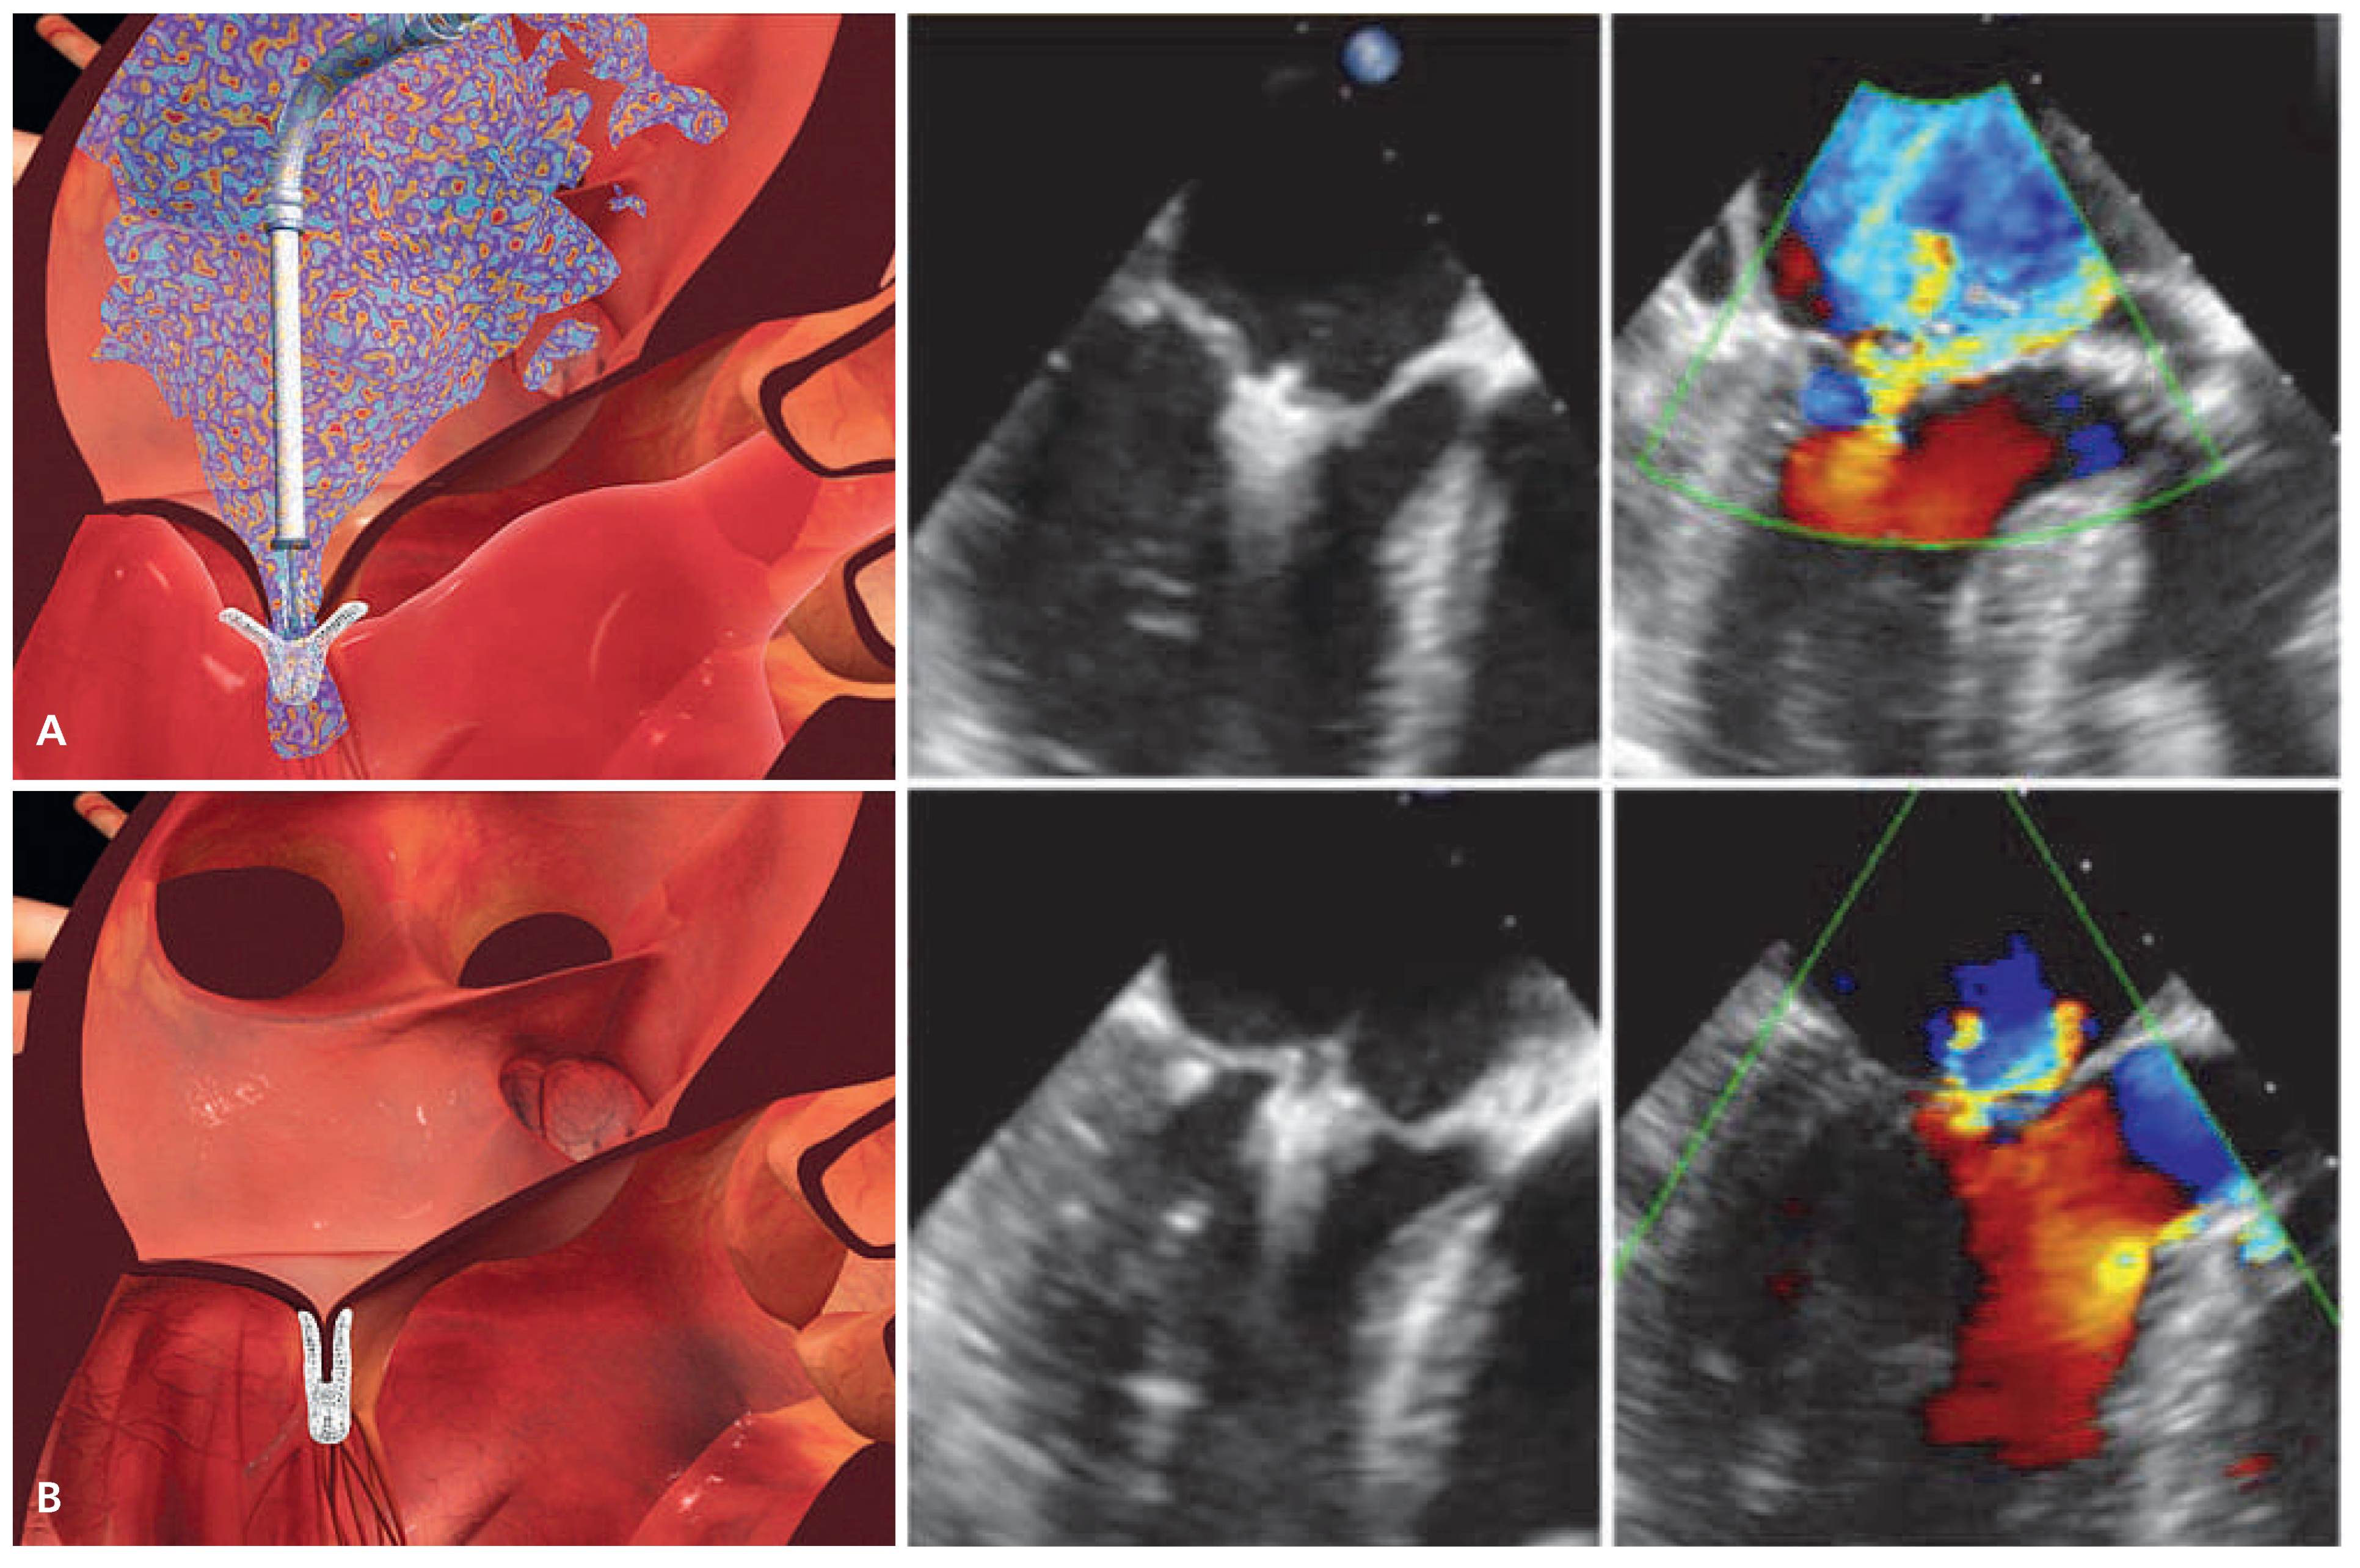

Figure 4. Schematic and echocardiographic images during MitraClip implantation. (A) After transseptal puncture, the MitraClip device is advanced over a steerable transseptal sheath, aligned with the origin of the MR jet and manoeuvered into the left ventricle. Thereafter, the clip is retracted with extended arms in order to grasp both mitral leaflets. The echocardiographic images shows adequate leaflet insertion, the MR jet is still considerable. (B) After closing both arms of the MitraClip device, the edges of the mitral leaflets are approximated thereby restoring coaptation and creating the typical double orifice mitral valve. After confirming adequate MR reduction on echocardiography, the clip is deployed and released from the delivery system. (Images [A, B] courtesy of Abbott Vascular. © 2012 Abbott Laboratories. All rights reserved.).

The MitraClip device consists of a percutaneously delivered MRI-compatible cobalt-chromium implant with two arms and two grippers which are used to grasp the opposing edges of the mitral leaflets (Figure 3). The procedure is generally performed under general anaesthesia with fluoroscopic and transoesophageal echocardiographic guidance and haemodynamic monitoring with a Swan-Ganz catheter in the pulmonary artery. The use of X-plane and 3D echocardiography is particularly helpful to visualise mitral valve anatomy and allow orientation of the device in 3D [27]. The device is delivered via transfemoral venous route. After transseptal puncture, the transseptal sheath is exchanged by a steerable 24-F guide catheter (which tapers to 22-F at the interatrial septum) through which the clip delivery system is advanced into the left atrium. Thereafter, the MitraClip device is manoeuvered under echocardiographic guidance, aligned with the origin of the regurgitant jet, and pushed below the level of the mitral leaflets into the left ventricle (LV). Careful consideration must be given to a perpendicular orientation of the clip arms and the leaflet edges before closing the clip (3D echocardiography). After opening the two arms of the clip, the device is retracted with extended arms (Figure 4A) and both leaflets are grasped by closing the grippers. Once adequate leaflet insertion is ascertained with echocardiography, the arms of the Mitra- Clip can be closed to approximate both scallops and restore coaptation. MR is immediately assessed by transoesophageal echocardiography and haemodynamic measurements, and if necessary, the device can be repositioned by reopening the arms and releasing the leaflets. If the desired result is obtained, the MitraClip is deployed and released from the delivery catheter (Figure 4B). Repeat clip insertion can be performed if MR reduction is suboptimal and the result is expected to improve with more than one clip. The only limitation to the number of clips implanted is the development of significant mitral stenosis.